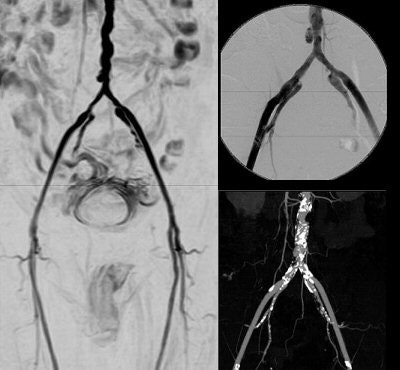

![]() |

| Noncontrast-enhanced vascular imaging on a 1.5-tesla scanner (Achieva). Left, gated subtraction MRA. Top right, digital subtraction angiography. Bottom right, CT angiography. Images courtesy of Philips Medical Systems North America and Hyogo Brain and Heart Center, Hygogo, Japan. |